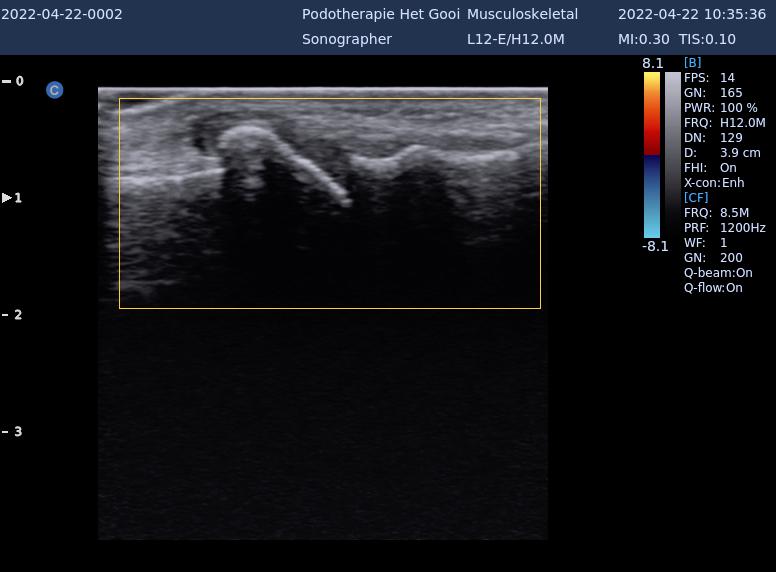

Verminderde beweeglijkheid grote teengewricht / verstijving grote teengewricht

Bij een hallux rigidus is de grote teen stijf doordat de gewrichten tussen de botjes van de teen versleten raken. De teen staat recht vooruit en kan moeilijk op en neer bewegen. Daardoor kan de teen niet meer goed afwikkelen. De meest voorkomende oorzaken zijn breuken in de teen, gewrichtsontstekingen en bijvoorbeeld artrose.